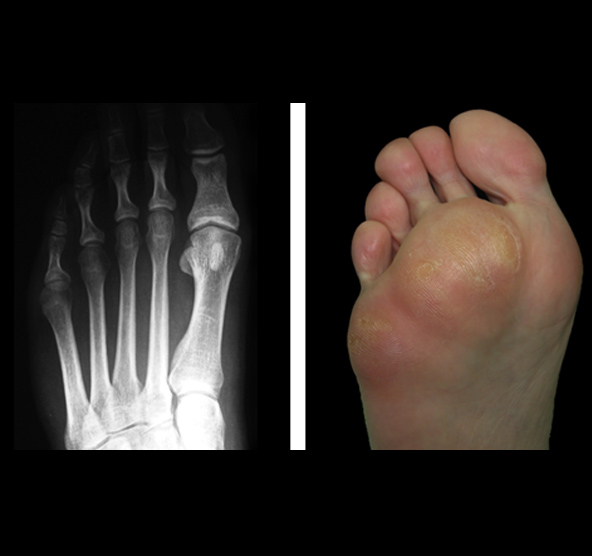

Las metatarsalgias mecánicas son debidas a la sobrecarga de los metatarsianos segundo al quinto y donde se suele apreciar la presencia de hiperqueratosis plantar, más conocida como callosidades que aparecen en las zonas de hiperpresión.